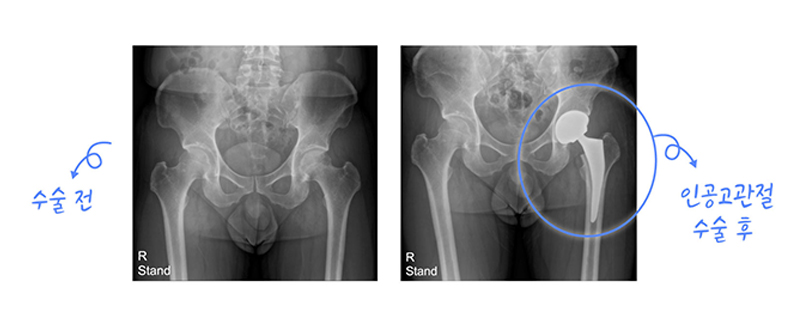

인공관절 치환술이란 관절염이나 특정 질환 또는 외상에 의해 더 이상 기능을 나타내지 못하는 즉 파괴된 관절의 일부분을 제거하고 인체공학적으로 제작된 기계를 삽입해서 관절의 운동 기능을 회복시켜주면서 통증을 없애는 수술을 말합니다. 인공관절 치환술의 목적은 관절 부위의 통증 해소와 운동 범위를 향상시키는 것입니다.

무혈성 괴사는 대퇴 골두로 가는 산소와 혈액 공급이 충분히 진행되지 않아 괴사가 발생하는 것을 말합니다. 괴사 후 관절이 망가지고 통증이 생기는 질환입니다. 대퇴골두에 혈액공급이 원활하지 않은 정확한 원인이 밝혀지지는 않았으나, 아래와 같은 요소들이 발병을 잘 일으키는 것으로 보고 있습니다.

괴사만으로는 통증이 발생하지 않기 때문에 특별한 초기 증상은 없으나,사타구니 부위가 자주 시큰거리거나, 차에 타고 내릴 때 또는 양반다리 자세가 불편하거나 통증이 있다면 질환을 의심해 보셔야 합니다. 필요한 경우 인공 관절로 수술을 시행합니다.